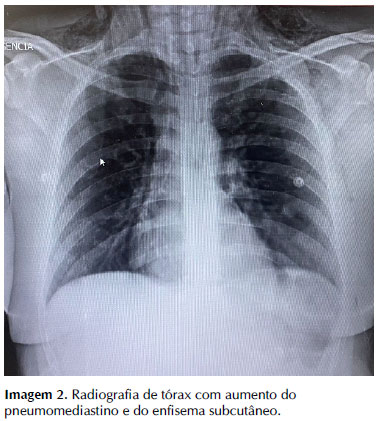

Gasometria arterial da manhã do 2° dia de internação mostrava: pH 7,44; pCO2 29; pO2 94; Lactato 2.6; HCO3 19,7; spO2 98% (com cateter de O2). Avaliação laboratorial não evidenciou achados adicionais, com marcadores dentro dos limites da normalidade. Avaliação radiológica demonstra radiotransparência bem delimitada da silhueta cardíaca e enfisema subcutâneo supraclavicular (no dia da admissão na observação), com leve aumento em radiografia de controle do dia seguinte (Imagem 1 e Imagem 2). Observa-se também, padrão de infiltrado reticular bilateral medial em terços inferiores dos pulmões: